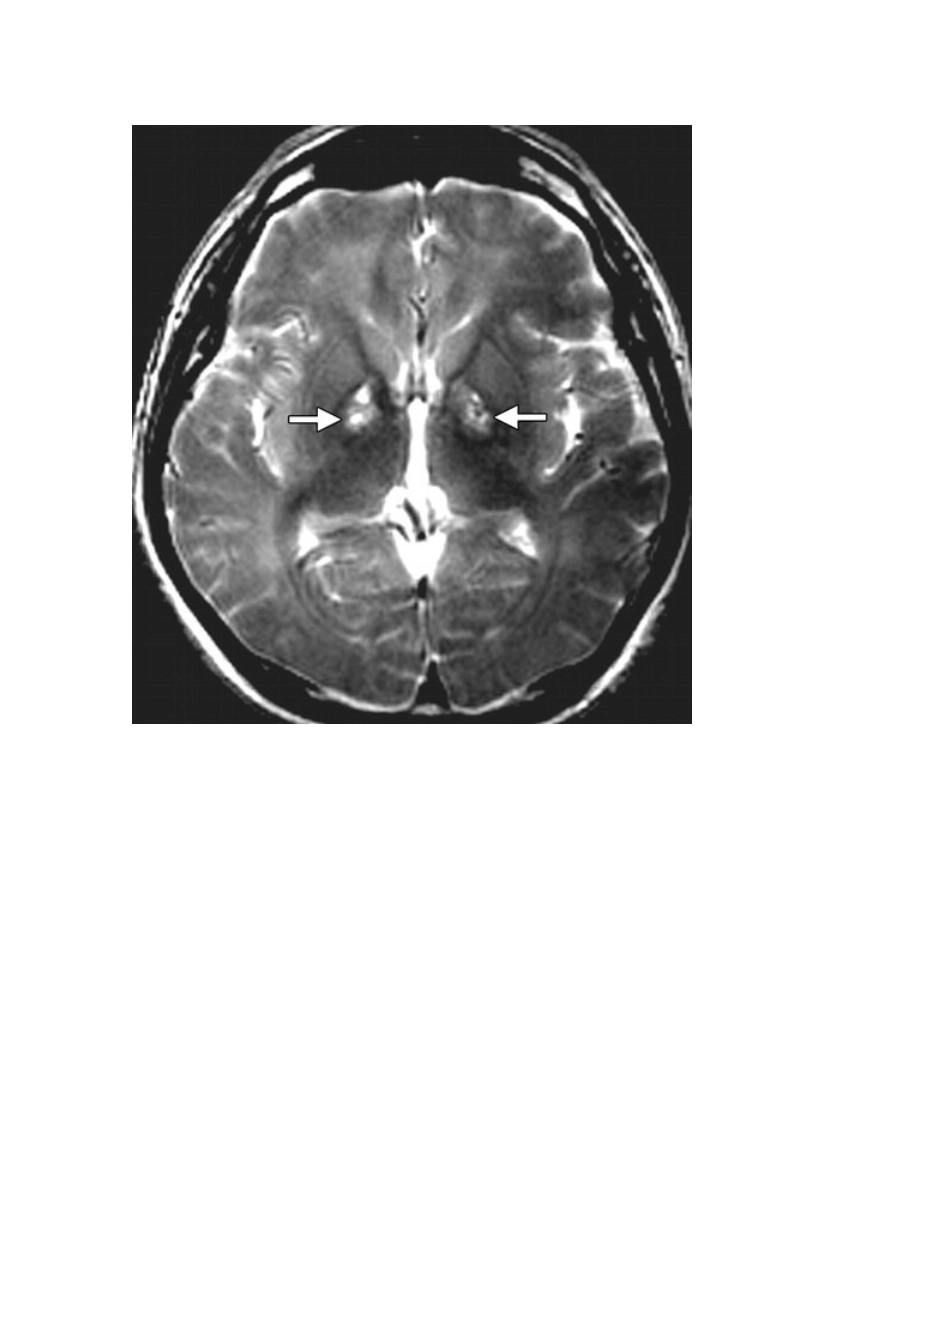

基底节区域异常的疾病逐一鉴别2025-07-08 来源:医脉通 许多种疾病都可表现为基底节和丘脑的异常,包括中毒、全身代谢性疾病、某些退行性疾病、血管异常等。本文将对不同疾病的表现特征进行介绍。进入正文之前,先来复习一下基底节区域的解剖吧:基底节的功能很复杂。这些结构主要涉及运动的产生,并且是锥体外系运动系统的一部分,同时也可以参加记忆、情绪和其他认知功能。由于壳核和苍白球富含线粒体、血管供应和神经递质,且代谢活性高、葡萄糖和氧的利用更多,因此易受代谢异常和许多全身性疾病的影响。丘脑则是由多个核团组成,负责感觉和运动信号的中继,参加意识、睡眠和警觉性的调节。因此,丘脑病变常常导致意识障碍和感觉异常。话不多说,马上进入正题——引起基底节及丘脑异常改变的疾病都有哪些?毒物中毒一氧化碳中毒➤ 表现为意外暴露或自杀未遂后急性认知障碍或昏迷➤ 具有苍白球受累倾向➤ 可能出现 T1WI 短信号和延迟脑白质病➤ DWI 上呈弥散受限33 岁男性,一氧化碳中毒后 4 周,轴位 T2WI 和冠状位 FLAIR 像显示双侧苍白球对称性高信号灶。深部白质对称性高信号区域与延迟性白质脑病表现一致。甲醇中毒➤ 壳核可出现缺血性坏死➤ 脑白质水肿是甲醇中毒的额外特征➤ 初始症状可包括视神经炎表现41 岁男性,甲醇中毒,精神状态改变、眼球后痛苦,增强 CT 显示豆状核、胼胝体、皮层下白质可见密度降低。肝脏疾病➤ 含氮废物通过血脑屏障造成长期毒性脑损伤➤ 锰沉积导致 T1WI 上苍白球、黑质高信号➤ 急性高氨血症可导致双侧基底节、岛叶皮质、扣带回水肿、T2WI 长信号和弥散受限➤ 肝移植后影像学改变可逆55 岁男性,肝硬化,T1WI 上可见双侧苍白球高信号。70 岁男性,急性高氨血症,肝硬化急性失代偿性肝功能衰竭,精神状态改变。影像学检查显示尾状核头、豆状核、岛叶皮质水肿、T2WI 高信号、DWI 弥散受限。非酮症性高血糖➤ 见于糖尿病控制不佳的患者,预后通常较好➤ 主要表现为急性舞蹈病症状、单侧抽搐、精神状态改变➤ CT 常表现为双侧(罕见单侧)苍白球或尾状核高密度➤ MRI 上表现为 T1WI 高信号,T2WI 多变信号68 岁女性,为未经控制的糖尿病患者,出现非酮症性高血糖,表现为舞蹈样症状发作。轴位 T1WI 显示双侧苍白球高信号。低血糖➤ T2WI 上可见双侧大脑皮层、海马、基底节长信号➤ 轻度低血糖表现为 MRI 上一过性白质异常,包括胼胝体压部、内囊和放射冠➤...